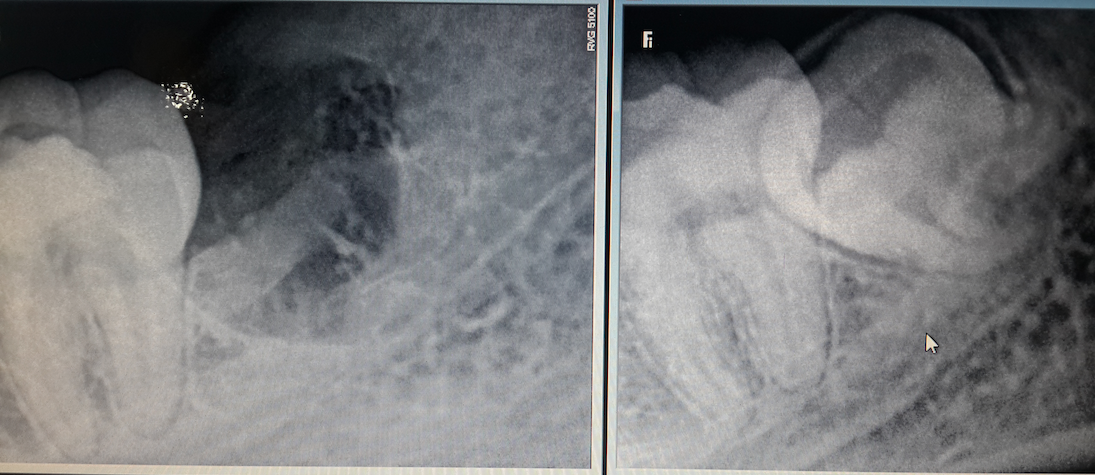

SUCCESSFUL TREATMENT STORIES